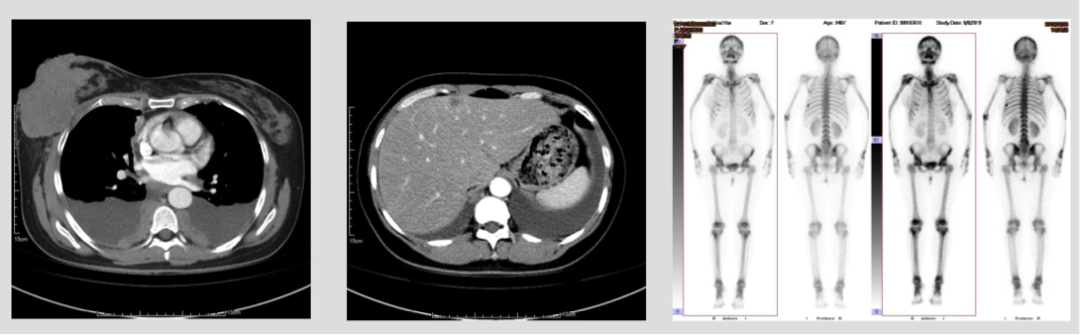

9岁的马女士来自农村,上有年迈的父亲,下有两个未成年的孩子。2018年4月的一天,马女士自觉左侧乳房刺痛感,后来乳房出现结节并逐渐增大,伴随皮肤表面颜色改变,但此...